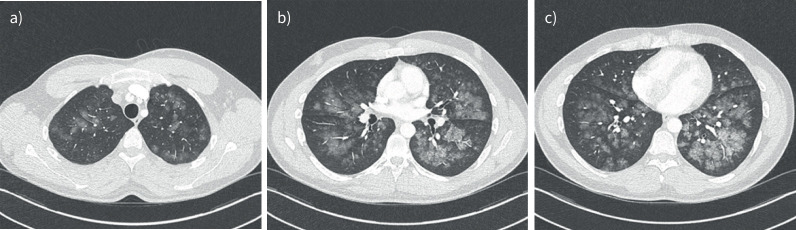

负压性肺水肿是术后患者急性呼吸窘迫的一个未被充分认识的原因。表现包括急性肺水肿和可能的DAH。及时认识和干预至关重要。https://bit.ly/4jYzOmn。

Negative pressure pulmonary oedema is an under-recognised cause of acute respiratory distress in post-operative patients. Presentations include acute pulmonary oedema and possibly DAH. Prompt recognition and intervention are essential. https://bit.ly/4jYzOmn.